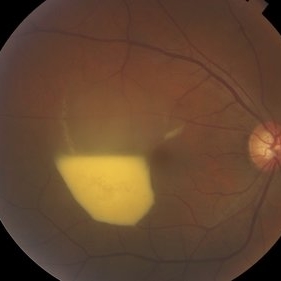

Retinal Hemangioblastoma PO PDT

Jun 12 2013 by Robert T. Wendel, MD

Retinal hemangioblastoma, 10 days post full fluence PDT.